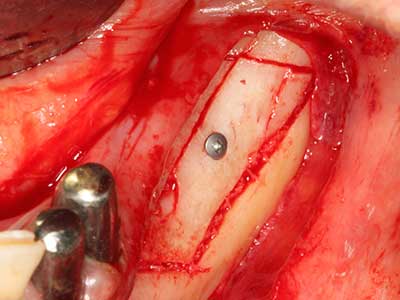

Fig. 1: Preparation of a bone cover with the Piezomed (W&H Salzburg, Austria).

Fig. 18: Preparation of a cortical cover with the piezo bone saw (Piezomed, W&H).

Fig. 19: Surgical site after neurolysis and removal of osteoma.

Fig. 20: The removed bone cover is re-adapted and fixed with an osteosynthesis screw (KLS Martin, Tuttlingen).